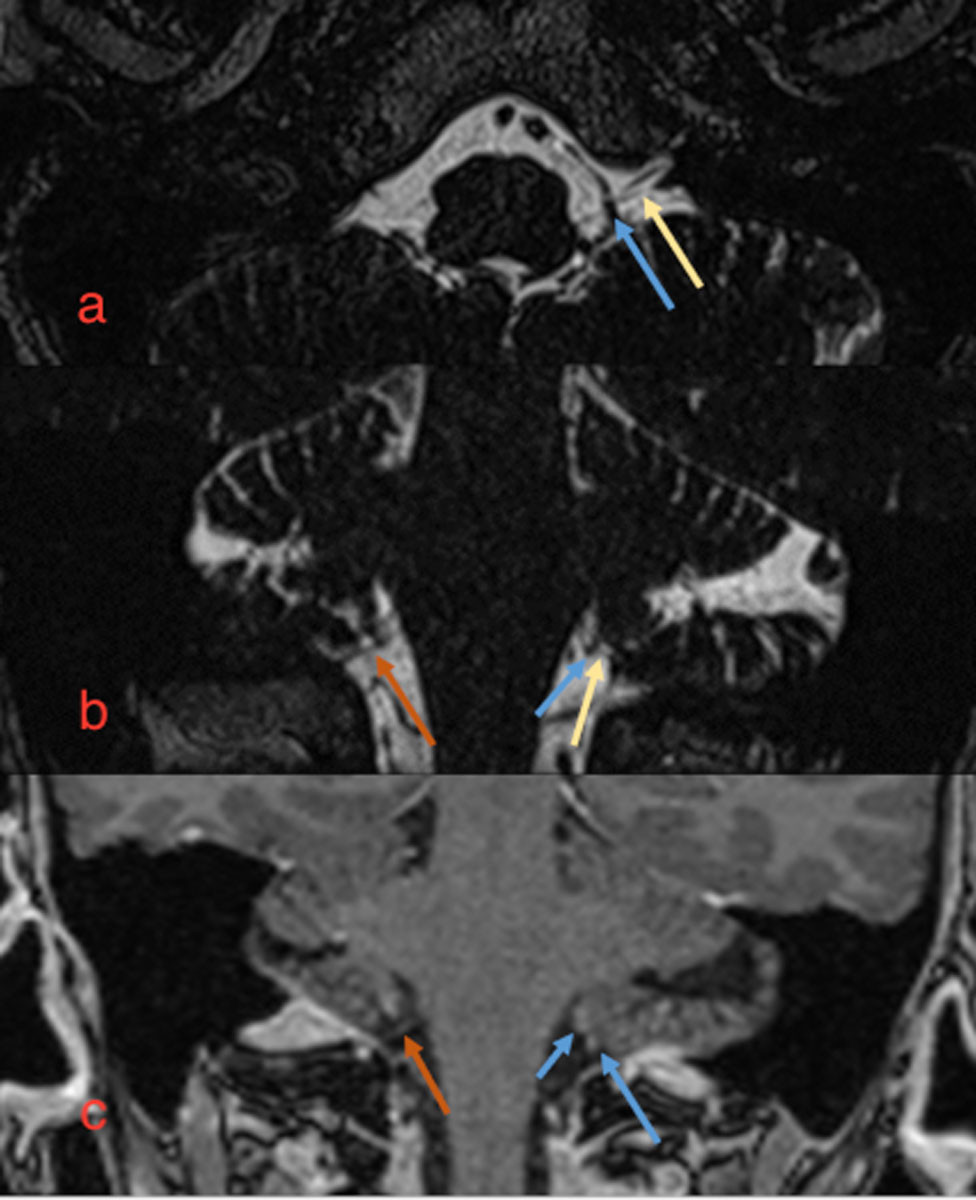

Maxillofacialkirurg mistenkte glossopharyngeusnevralgi og henviste til MR med intravenøs kontrast for å kartlegge om det forelå tegn til påvirkning av nerven fra omkringliggende blodkar. MR (3D T2 turbo spin echo og fett-supprimert T1 etter intravenøs kontrast) av caput og skallebasis avdekket en asymmetri rundt n. glossopharyngeus. Nervens forløp på høyre side var upåfallende, mens langs nerven på venstre side ved den cerebellopontine vinkelen lå flere små karstrukturer tolket som små piale vener (figur 1). Det var ingen arterier med relasjon til nerven eller tegn til denervasjon av stylopharyngeus. Det var et lite, rundaktig kontrastopptak ved dura i foramen magnum på venstre side, og pasienten ble derfor undersøkt med CT angiografi av pre- og intracerebrale kar for å utelukke aneurisme. CT viste normale pre- og intracerebrale kar og ingen aneurismatisk utvidelse av a. cerebelli inferior posterior. Det ble bemerket forlengede processus styloideus bilateralt.

Pasienten ble henvist for vurdering av dekompresjonskirurgi på bakgrunn av glossopharyngeusnevralgi, og hun ble vurdert av nevrokirurg fem måneder etter symptomdebut. Tilstanden ble vurdert som glossopharyngeusnevralgi med nevropati. Det kliniske bildet ble oppfattet å passe med funnet på MR med tilliggende kar mot n. glossopharyngeus på venstre side, og pasienten ble søkt til mikrovaskulær dekompresjonskirurgi. Hun ble operert et halvt år etter symptomdebut. Peroperativt fant man en grovkalibret vene langs hele forløpet av n. glossopharyngeus på venstre side som passet med MR-funnet. Venen ble fridissekert og fiksert bort fra nerven. Postoperativt forløp var ukomplisert, sett bort fra noe kvalme og svimmelhet. Pasienten ble utskrevet etter to dager til lokalsykehus for videre mobilisering. Ved kontroll hos nevrolog elleve uker etter operasjonen oppga pasienten betydelig bedring av smertene, med kortere og mindre intense anfall enn tidligere. Ett år etter kirurgi hadde hun ytterligere forbedring, og hun er fortsatt i bedring to år etter operasjonen. Hun kan fremdeles merke plager ved kuldeeksponering og når hun er sliten. Hun har vært gjennom rehabilitering for å normalisere tunge- og svelgemotorikk, og kroppsvekten har normalisert seg (etter et vekttap på totalt 10 kg fram til operasjon).

Glossopharyngeusnevralgi kan oppstå sekundært til kompresjon av n. glossopharyngeus fra tumor i cerebellum/pons-området, aneurisme, ekstrakraniell tumor i orofarynks, overvekst av processus styloideus (Eagles syndrom), disseksjon av a. vertebralis, tonsilitt og periotonsillær abscess (9, 13). Eagles syndrom skyldes forlengede processus styloideus (> 30 mm) med påfølgende kompresjon av nærliggende nervestrukturer som gir smerter i hals og svelg, typisk ved rotasjon og sidebøy av nakken (6). Hos vår pasient viste CT forlengede processus styloideus, men det var ingen tegn til kompresjon fra denne på n. glossopharyngeus. Dette, i tillegg til fravær av typiske kliniske funn, gjorde at man utelukket Eagles syndrom som årsak, og tolket forlengede processus styloideus som normalvariant. MR viste imidlertid en nær relasjon mellom n. glossopharyngeus og et blodkar i bakre skallegrop som er angitt som en vanlig årsak til glossopharyngeusnevralgi (9, 13).